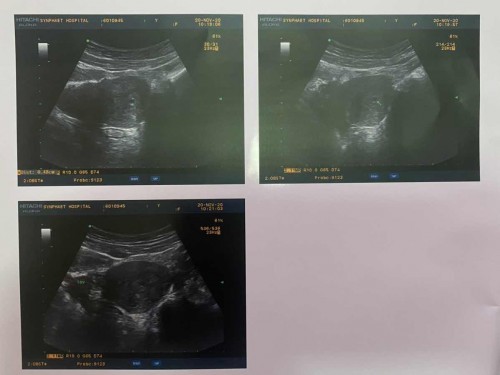

ขอเล่าเรื่องก่อนนะคะ ปจด.เรามาวันแรกครั้งล่าสุดคือ 9/10/63 ผ่านมาจนถึงวันที่ 17/11/63 ปจด.ยังไม่มาเราเลยซื้อที่ตรวจมาตรวจ สรุปว่าขึ้น 2 ขีดค่ะ เราเลยตรวจซ้ำวันที่ 17-19/11/63 ขึ้น 2 ขีดทั้ง 3 วัน เรากับแฟนเลยไปหาหมอค่ะ วันแรกหมอก็ถามรายละเอียดทั่วไป แล้วให้ U/S หน้าท้องหมอแจ้งว่าถุงครรภ์ประมาณ 4 มล. ยืนยันว่าตั้งครรภ์ อายุครรภ์น่าจะเข้า 5 Week แต่ยังไม่เห็นตัวหรือได้ยินเสียงหัวใจ เลยนัดให้มาตรวจอีกครั้งวันที่ 9/12/63 แล้วก็ให้ยากลับบ้าน หลังจากนั้นเราก็ใช้ชีวิตปกติ กินยาตามที่หมอให้ปกติ จนวันที่ 27/11/63 เรามีอาการปวดท้องด้านซ้ายมากกว่าทุกวัน แต่ไม่มีเลือดออก (ปกติปวดหน่วงๆหมอบอกมดลูกขยายตัว) เราเลยไปหาหมอ หมอให้ U/S หน้าท้องอีกครั้ง หมอแจ้งว่าครภภ์เราผิดปกติ เพราะเมื่อวันที่ 20/11/63 มีขนาด 4 มล. มาวันที่ 27/11/63 เพิ่มมาเป็น 7 มล.ซึ่งมันน้อยกว่าอายุครรภที่หมอนับ เลยให้เรา U/S ทางช่วงคลองอีกทีพร้อมกับตรวจเลือด ผลการตรวจ U/S ทางช่องคลอดกับการตรวจเลือดหมอแจ้งว่าน่าจะเป็นการนับครรภ์ที่คลาดเคลื่อน เพราะค่าฮอโมนได้อยู่ที่ 1,400 น่าจะพึ่ง 4 weekทำให้ถุงตั้งครรภ์เล็กและฮอโมนต้ำ เลยนัดเรามาวันที่ 29/11/63 อีกครั้ง วันที่29/11/63 เรามาตามนัดหมอโดยที่ตั้งแต่ 27-29/11/63 ไม่มีอาการปวดท้องและไม่มีเลือดออกเลย พอถึง รพ.เราก็ทำการเจาะเลือดและนั่งรอพบหมอ พอผลเลือดออกเราก็เข้าไปพบหมอ พอหมอเห็นผลเลือดก็แจ้งเลยว่าครรภ์เราไม่ปกติ เพราะค่าฮอโมนขึ้นมาแค่นิดเดียวจาก 1,400 เป็น 1,600 ซึ่งถ้าคนท้องปกติต้องเพิ่มเป็น 2 เท่าทุก 2 วัน ตอนนี้ให้ตัดเรื่องการตั้งครรภ์ปกติออกไปเลย เหลือแค่ลุ้นว่าจะแท้งธรรมชาติ ขูดมดลูก หรือท้องนอกมดลูก 😭😭 หมอเลยนัดอีกครั้งวันที่ 4/12/63 คำถามคือ 1.หมอยังดูไม่ออกเหรอคะว่าท้องในหรือนอกมดลูก 2.ตั้งแต่รู้ว่าตั้งครรภมีอาการปวดหน่วงข้างซ้ายตลอดจดปวดหนักวันที่ 27/11/63 แต่ไม่มีเลือดออกเลย มีโอกาสที่จะท้องในหมดลูกไหมคะ 3.ควรเปลี่ยน รพ.เพื่อตรวจครรภ์ใหม่ไหมคะ รบกวนแม่ๆด้วยนะคะ 😭😭😭